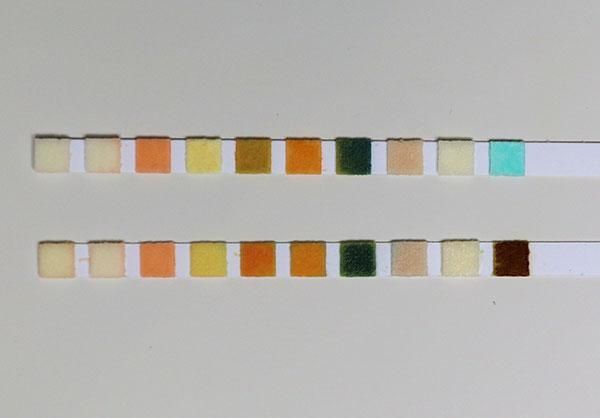

These relatively simple tests indicate the presence or absence of a range of different chemicals that in turn indicate infections, problems in the kidneys or other problems such as diabetes that can result in glucose in the urine.

Example: Glucose oxidase is the enzyme found on dip-sticks used for testing urine for glucose

The enzyme is mixed with peroxidase and a blue dye. If the urine contains no glucose then the dye stays blue. However, if there is glucose present, the enzyme breaks up the glucose and releases hydrogen peroxide. This in turn reacts with the other chemicals, turning the dye from blue to green to brown depending on the glucose levels.

Enzyme technology enables doctors to see that the only abnormality in the urine of this patient is the presence of glucose.